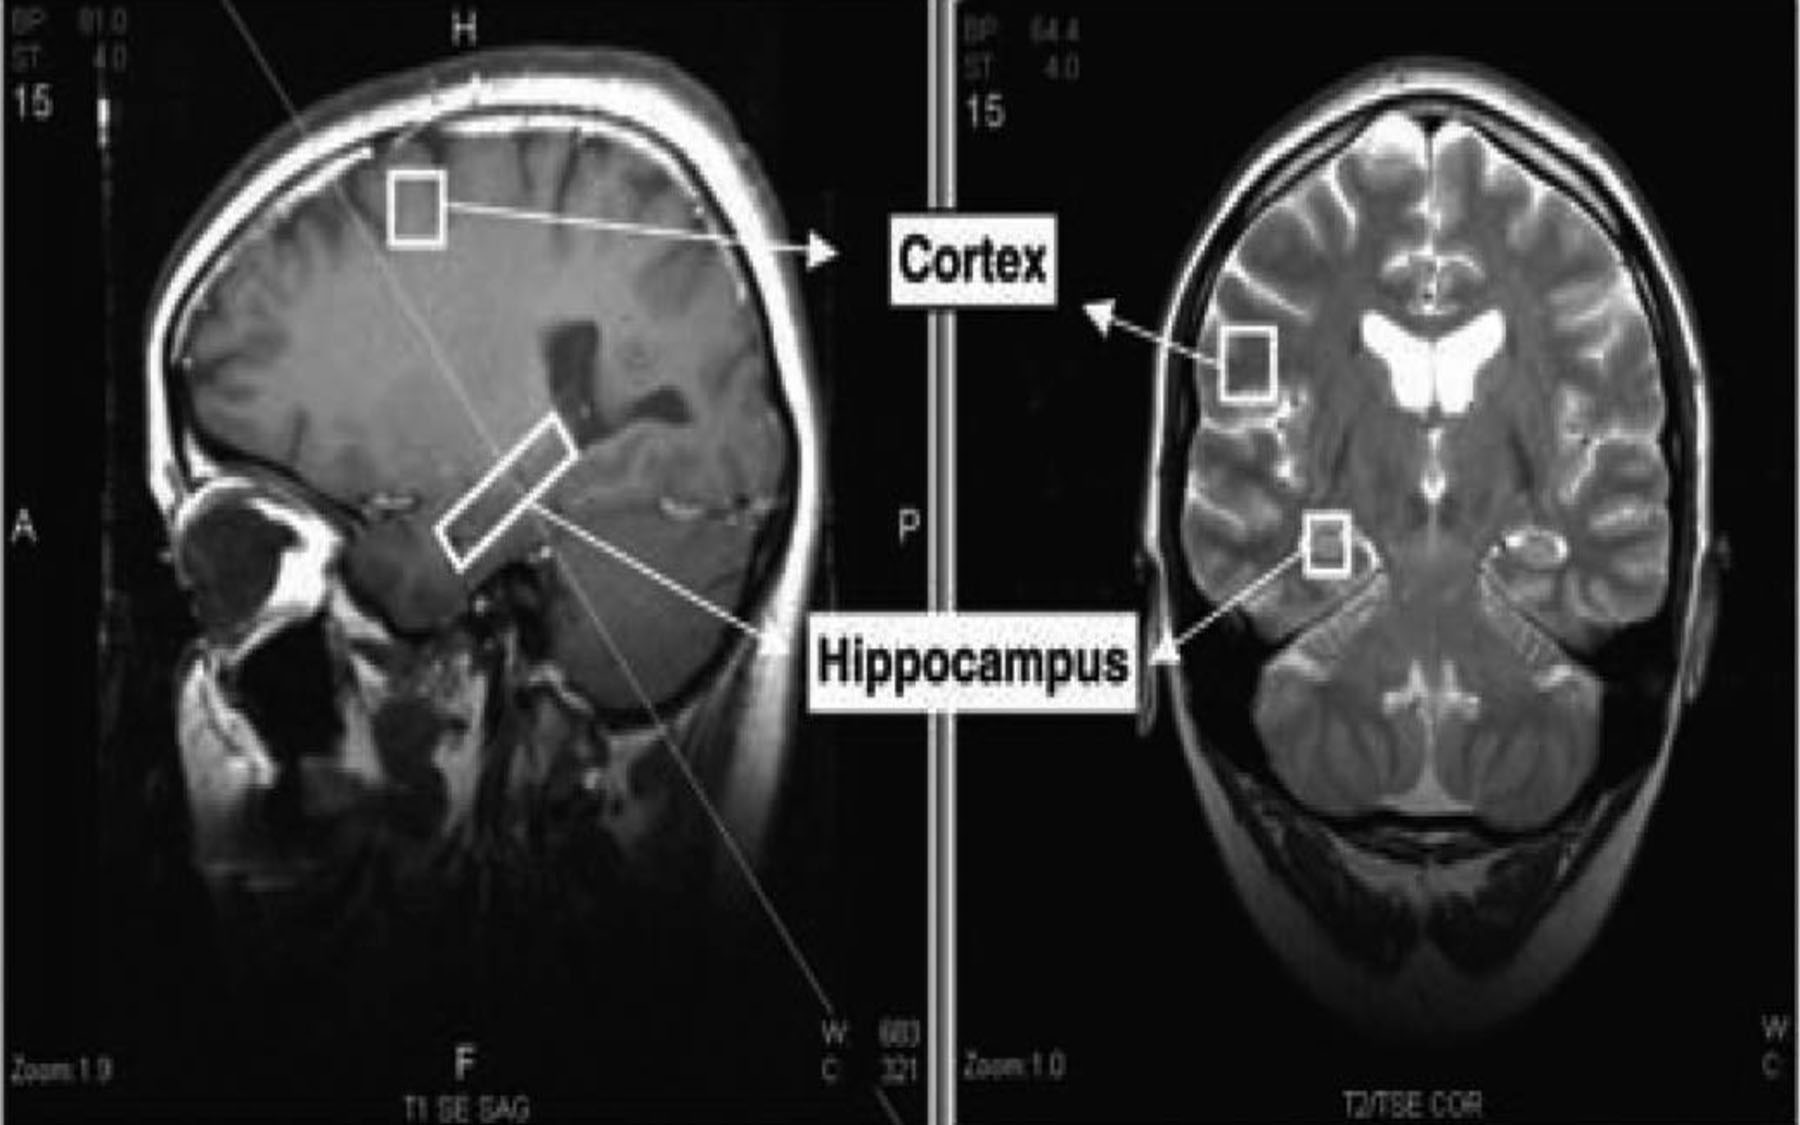

The biomarker is a lipid molecule whose presence the scientists were able consistently to detect in a part of the brain called the hippocampus where new nerve cells are known to be generated. The marker was not detected in the cortex and other parts of the brain where this process, called neurogenesis, does not occur in healthy adults.